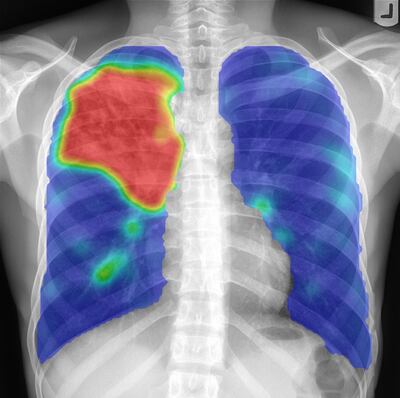

A: I studied physics and completed a PhD in medical image analysis in 1996, developing computer programs that analyse chest x-rays using artificial intelligence (AI). At the end of the 1990s we wanted to put digital chest x-ray units with AI software in countries where there was a lot of tuberculosis, because it accommodates faster, more widespread screening, without the need to develop images on film. However, digital x-ray equipment was too expensive at that time.

In 2012, deep learning broke through and made AI for medical images more popular. I moved to a university in the east of the Netherlands and set up a group of 70 researchers analysing medical images. Five years ago, we began working with pathology departments to digitize images. The trouble is, when stored for medical use, these very big images take up a lot of space. Departments are therefore deleting all their images after three months – so we can’t use them for deep learning. As storage systems become cheaper, we are closer to solving this. We will see all pathology departments digitized within the next ten years, I’m sure.